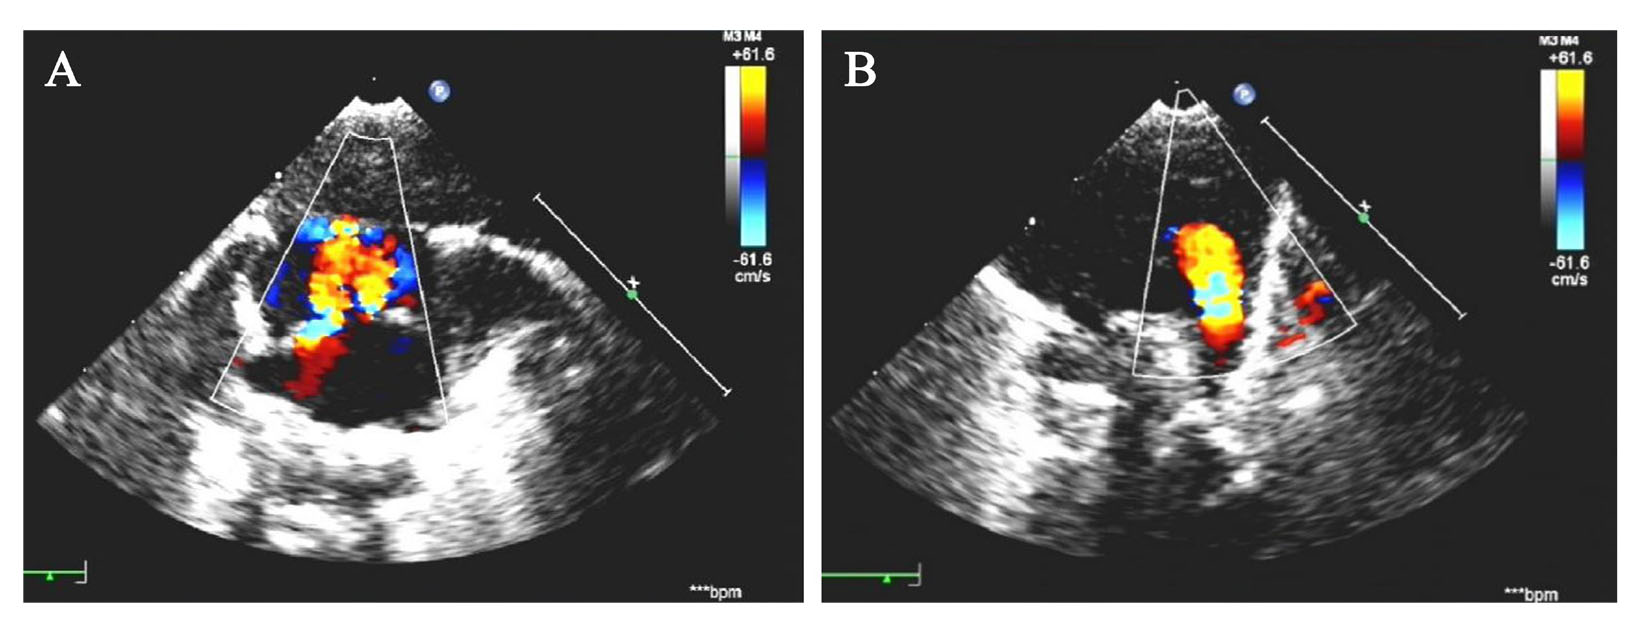

患儿男,出生7 d,系孕36+3周自然受孕早产儿。母亲G1P1,产前未在本院规律产检,孕早期唐氏综合征筛查未见异常,停经14+周外院彩色多普勒超声(彩超)提示胎儿大小约12+4周,颈项透明层厚度(NT)值为2.5 mm。孕中期外院三维彩超未见明显异常。母亲36+3周外院产检发现胎心持续反应差,无下腹部疼痛,阴道无流血、流液,自觉胎动如常,予胎心监护、静脉输液治疗未见改善,遂至我院急诊就诊,拟诊胎儿宫内窘迫,行剖宫产,娩出一男性新生儿。患儿出生时体重2 850 g,身长48 cm,出生后查体反应可,前囟平软,哭声不扬,口唇微绀,双手多指畸形(六指)。辅助检查:血尿粪常规,甲状腺功能,电解质,肝功能等均正常。性激素6项:睾酮3.03 nmol/L,卵泡刺激素< 0.30 IU/L,催乳素1 431.6 mIU/L,孕酮6.89 nmol/L,黄体生成素< 0.07 IU/L,雌二醇88.02 pmol/L。彩超提示:右侧阴囊内睾丸缺如,右侧腹股沟隐睾,左侧睾丸及附睾未见明显异常;肺动脉高压(重度),动脉导管未闭,房间隔缺损(多孔,继发孔型),室间隔小缺损(肌部),三尖瓣反流(轻度),右心房右心室增大,左心室收缩功能正常,见图1。患儿父母非近亲结婚,否认家族遗传病史,无既往病史。

图1 一例PMS患儿的彩超结果

注:A为房间隔缺损;B为动脉导管未闭。